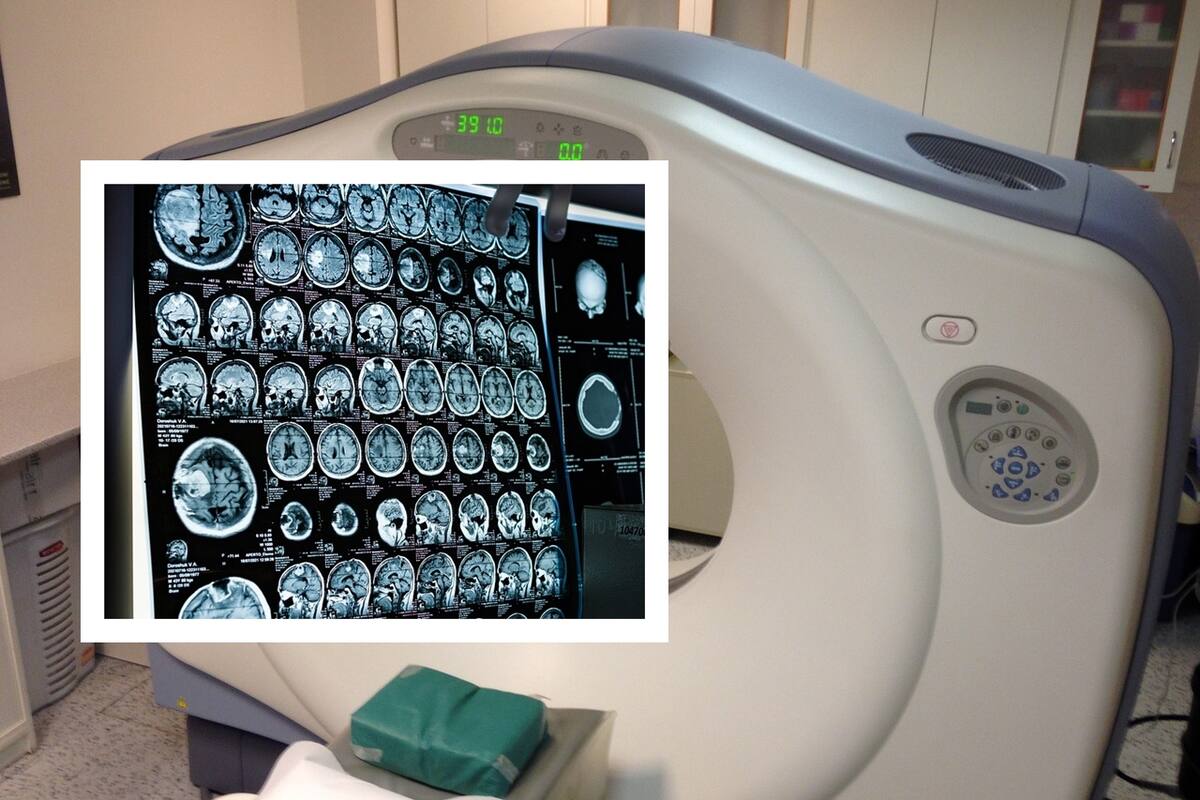

HERMOSILLO, Sonora.- El Centro Estatal de Oncología cuenta con un equipo que realiza exclusivamente tomografías con fines de simulación para tratamientos de radioterapia, el cual no ha presentado fallas y se encuentra en funcionamiento, afirmó IMSS – Bienestar en Sonora.

El objetivo de dicho equipo es tomar imágenes mediante tomografía que son exportadas al sistema de planeación, donde fiscos médicos junto con médicos especialistas en radio-oncología planean y establecen el tratamiento a recibir de manera individualizada cada paciente, posteriormente estas imágenes pasan al acelerador lineal (equipo de radioterapia).